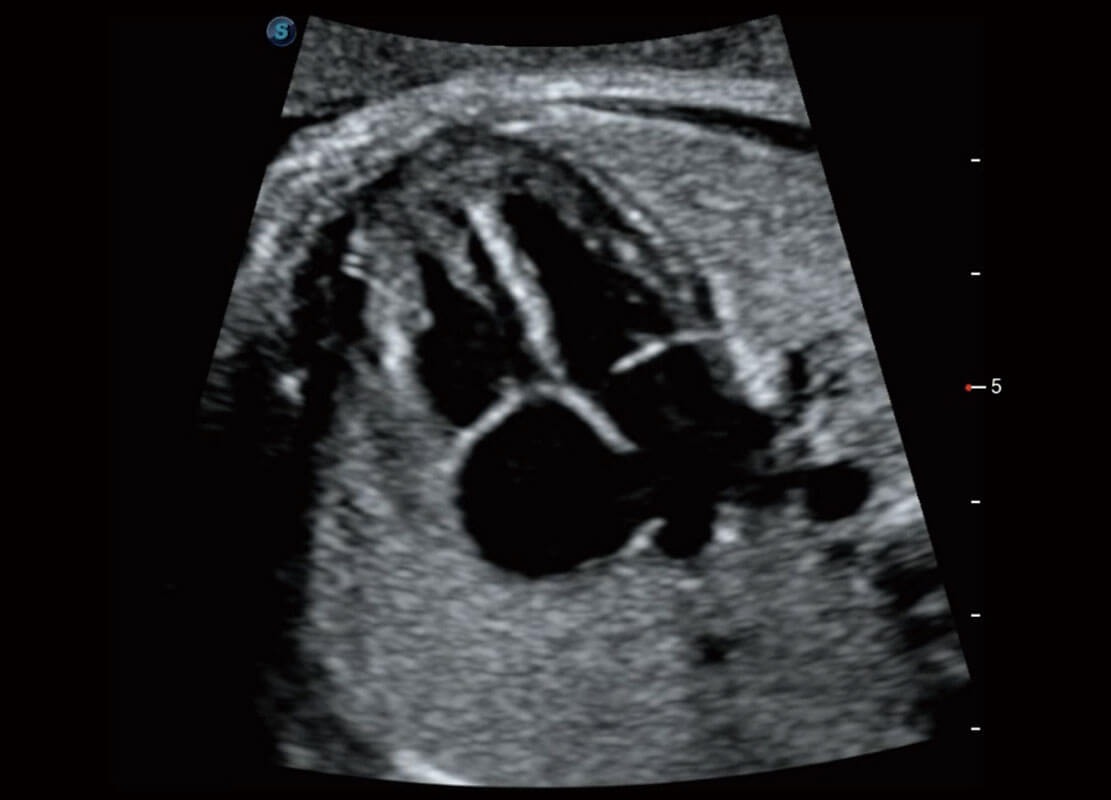

P60在胎儿早孕期超声筛查中为您带来优异的图像质量。

早孕-胎心

高分辨率容积成像-早孕胎儿

胎儿体循环

光影成像-孕囊